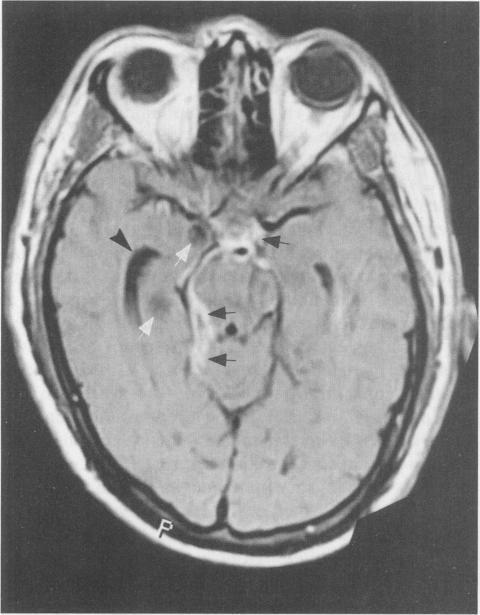

High-dose praziquantel with cimetidine for refractory neurocysticercosis: a case report with clinical and MRI follow-up.

West J Med. 1999 Feb;170(2):112-5.